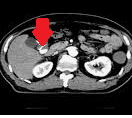

CT κοιλίας. Κόκκινο βέλος — Τυφλίτιδα. Σημαντική πάχυνση τοιχώματος τυφλού (Ευγενική παραχώρηση Dr. V. Penopoulos)